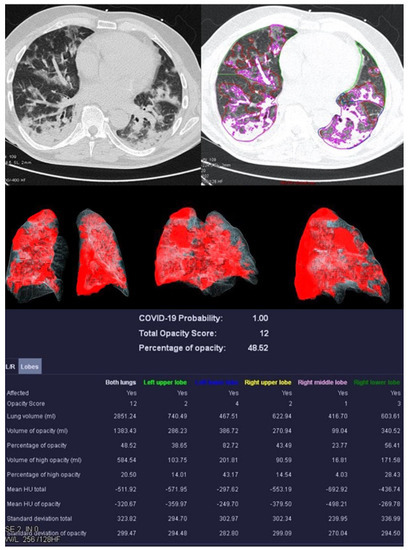

Figure 3.

Examination results of a 61-year-old patient with a severe course of COVID-19 pneumonia. Incipiently consolidating ground glass opacities and sharply defined ground glass opacities with reticulations and crazy-paving patterns.